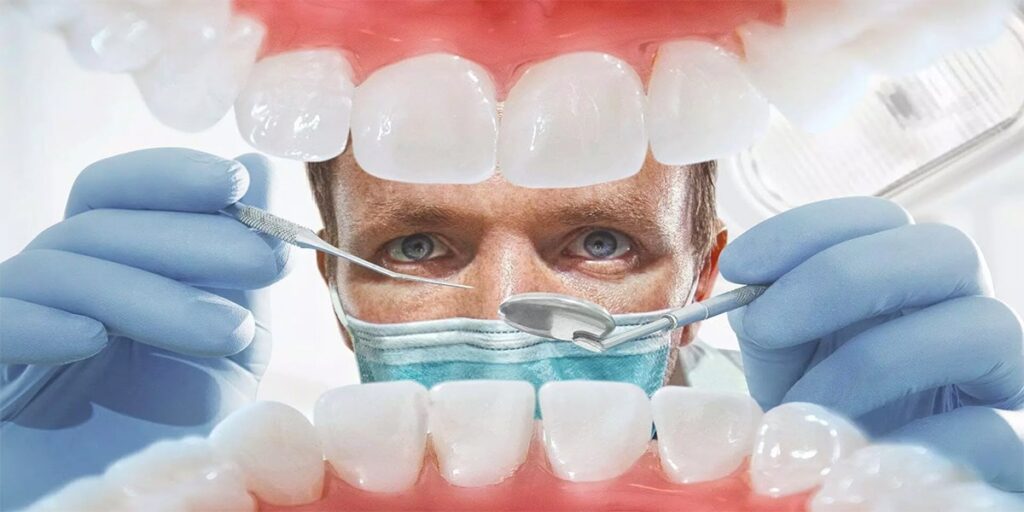

معتبر ترین و مجهز ترین کلینیک تخصصی دندانپزشکی در ایران

Best Dental Office with the Best Tools and Doctors in IRAN

? Why Choose Sana